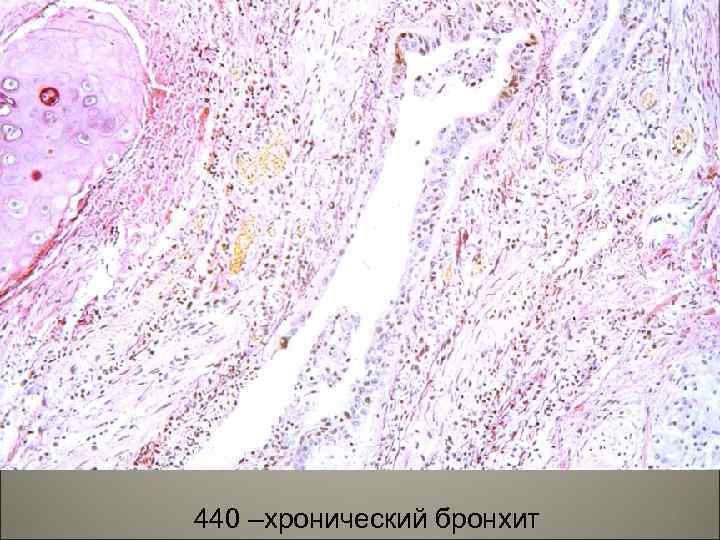

• Морфологически выделяют: 1. Хронический гнойный бронхит, 2. Хронический катарально-гнойный бронхит, 3. Хронический деструктивный бронхит. 27

• В эпителии при хроническим бронхите наблюдается: десквамация, некроз, метаплазия, атрофия желез и замещение их соединительной тканью, уменьшение количества бокаловидных клеток, необратимые изменения в мышцах, хрящах, серозной оболочке, при этом бронх превращается в трубочку из соединительной ткани. 28